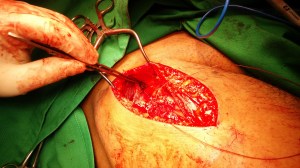

Suture anchor is applied to the anterior inferior iliac spine:

The torn rectus femoris is repaired to the footprint.